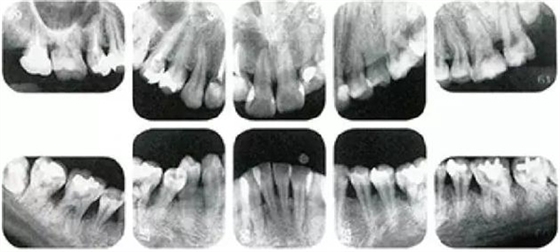

右邊參考病例

①的患者是35歲女性。4~10mm的牙周袋和大量的牙石。特別是在左上、右下、左下的磨牙處能看到大量牙槽骨吸收。這名患者是慢性牙周炎,僅在磨牙處有局部由風(fēng)險(xiǎn)因子導(dǎo)致(解剖學(xué)形態(tài))導(dǎo)致的重度病癥發(fā)展。

另一方面25歲女性的參考病例

②將會(huì)是什么樣的呢?左上、右下、左下的磨牙處有大量牙槽骨吸收,考慮到其發(fā)病年齡,斷定為是侵襲性牙周炎局部型。

但是實(shí)際上參考病例①和②是同名患者,①是②10年后的狀態(tài)。這名患者間隔10年后來就診,讓我們可以確認(rèn)到癥狀的變化。

在日常臨床中,還毫無自覺中病情發(fā)展的患者很多,如果不知道患者年齡=很難下診斷是頻繁的。

●參考病例① 35歲女性

35歲女性。妊娠4個(gè)月。過去雖然接受過刷牙指導(dǎo),但菌斑控制狀態(tài)依然不理想?;颊哂邪l(fā)現(xiàn)自己刷牙時(shí)牙齦出血。

●參考病例② 25歲女性

25歲女性。菌斑控制狀態(tài)不好。齦溝除磨牙處外全在3mm以下,X光照片上左上、右下、左下的第一磨牙上有垂直性骨吸收。這個(gè)病例是參考病例①10年前的狀態(tài),是典型的侵襲性牙周炎局部型。